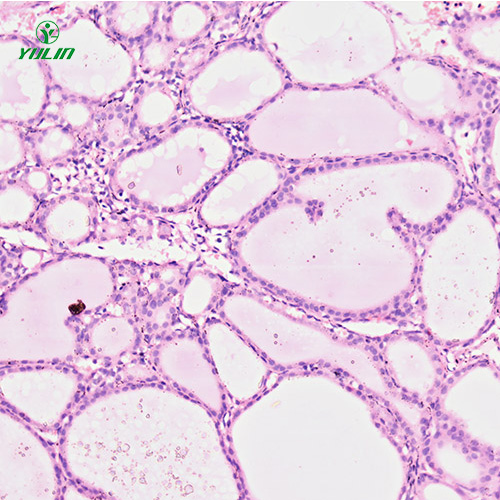

生物玻片是用顯微鏡研究生物時必不可少的玻璃片。你知道如何更好地制作它嗎?如果你不知道,不妨學(xué)習一下人內(nèi)分泌系統(tǒng)疾病標本片的制作注意事項。

眾所周知,人內(nèi)分泌系統(tǒng)疾病標本片需要在顯微鏡下觀察,但是很多用戶不知道如何更好的使用人內(nèi)分泌系統(tǒng)疾病標本片。所以給大家講解一下如何使用人內(nèi)分泌系統(tǒng)疾病標本片。

說到人內(nèi)分泌系統(tǒng)疾病標本片,我們都會想到實驗課上做的一些實驗。我們都知道人內(nèi)分泌系統(tǒng)疾病標本片可以幫助我們更好地學(xué)習生物。然而,在制作人內(nèi)分泌系統(tǒng)疾病標本片的過程中,不可避免地會出現(xiàn)一些問題。這里了解一下制作過程中會遇到哪些問題。

我們都知道人內(nèi)分泌系統(tǒng)疾病標本片對研究生物細胞的重要性,我們都知道一旦出現(xiàn)問題,就會對研究結(jié)果產(chǎn)生嚴重的后果。你知道影響人內(nèi)分泌系統(tǒng)疾病標本片檢測的因素有哪些嗎?如果你不知道,請跟隨我們了解一下。